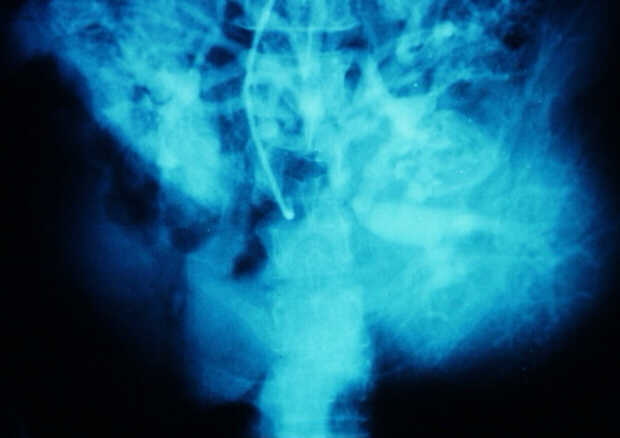

Diagnosis: Angiography

Giuseppe Morelli Coppola, Raffaella Niola, Franco Maglione

Unità Operativa di Radiologia Vascolare ed Interventistica, Azienda Ospedaliera "A. Cardarelli". Napoli, Italy